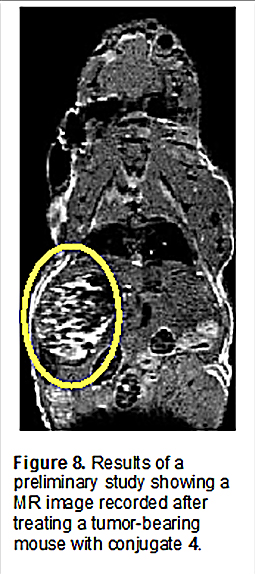

Unfortunately, efforts to translate the promise seen in the in vitro studies into xenograft murine tumor models proved challenging. Although in one preliminary study, evidence of tumor localization was seen through MR imaging (Figure 8), difficulties were encountered in finding a formulation adequate to allow for multiple tail vein injections.

As a consequence, initial seemingly promising tumor uptake and growth inhibition results proved difficult to reproduce. A decision was thus made at this juncture to redesign our approach and 1) rely on Pt(IV) prodrug forms of FDA-approved platinum anticancer agents and 2) tether the Pt(IV) payload through the tripyrrane substituents, rather than the ortho-phenylenediamine subunit, as in the case of 3 and 4. This led to the production of second generation texaphyrin-platinum prodrug conjugates as detailed below.